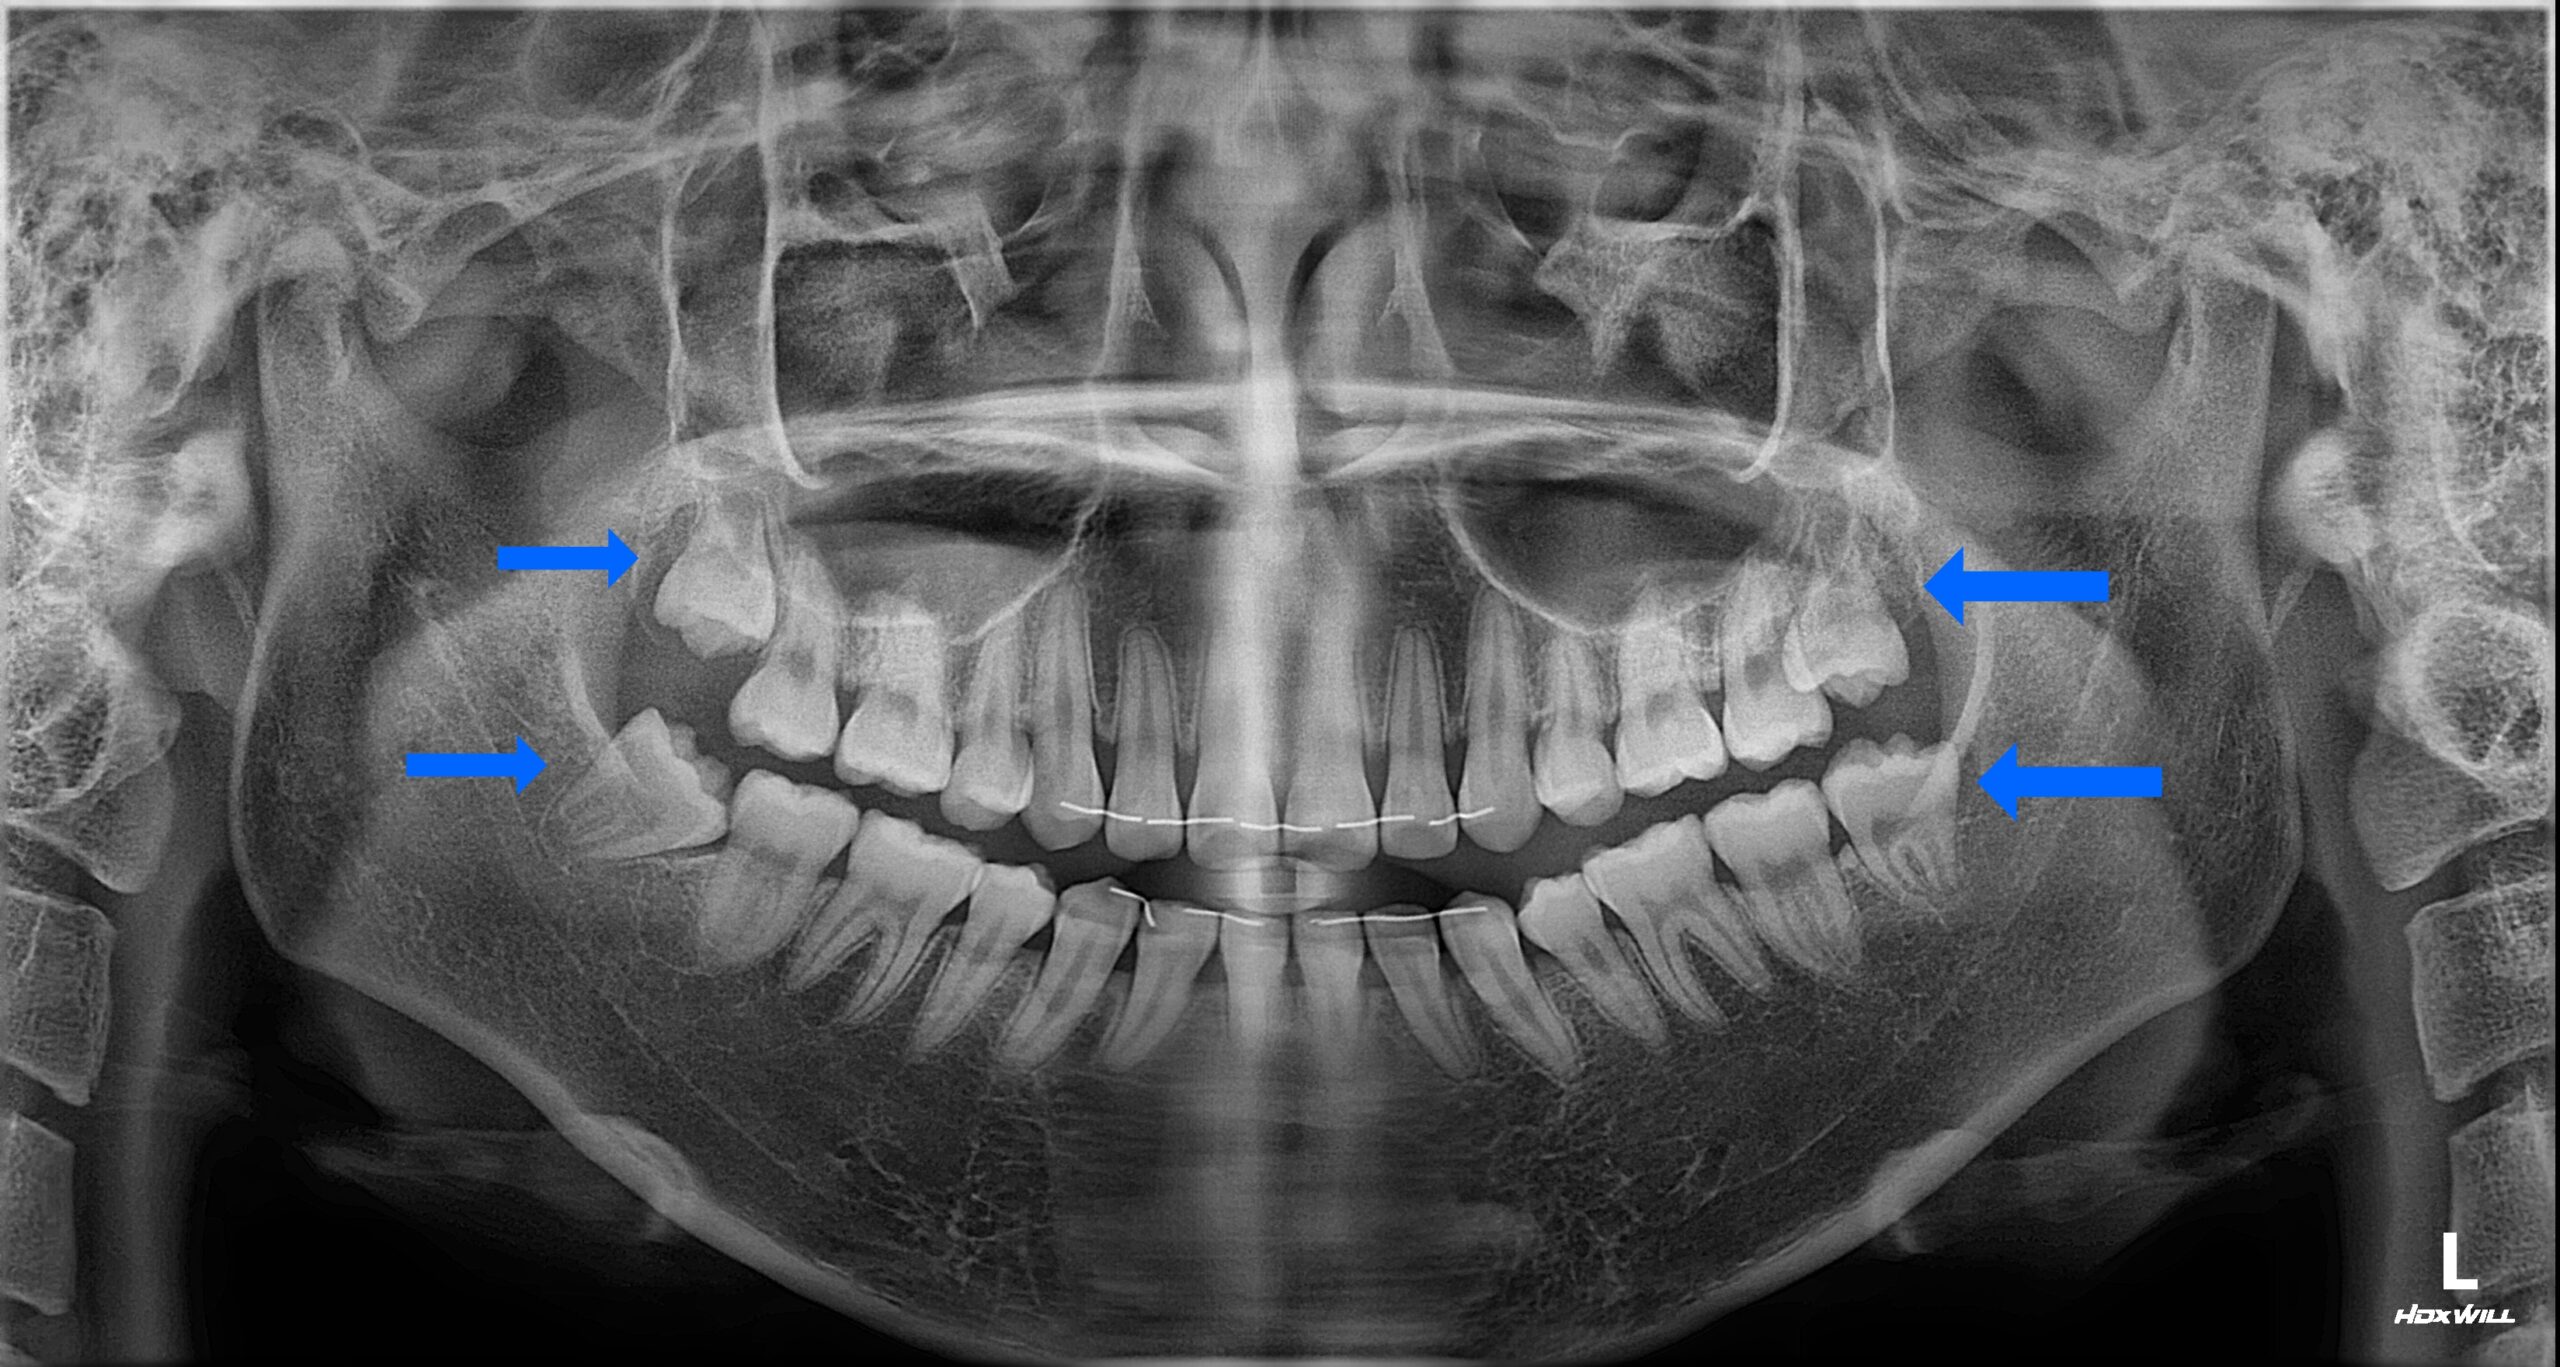

수면 치과 치료 전 파노라마 X-ray 다수 문제 부위 진단